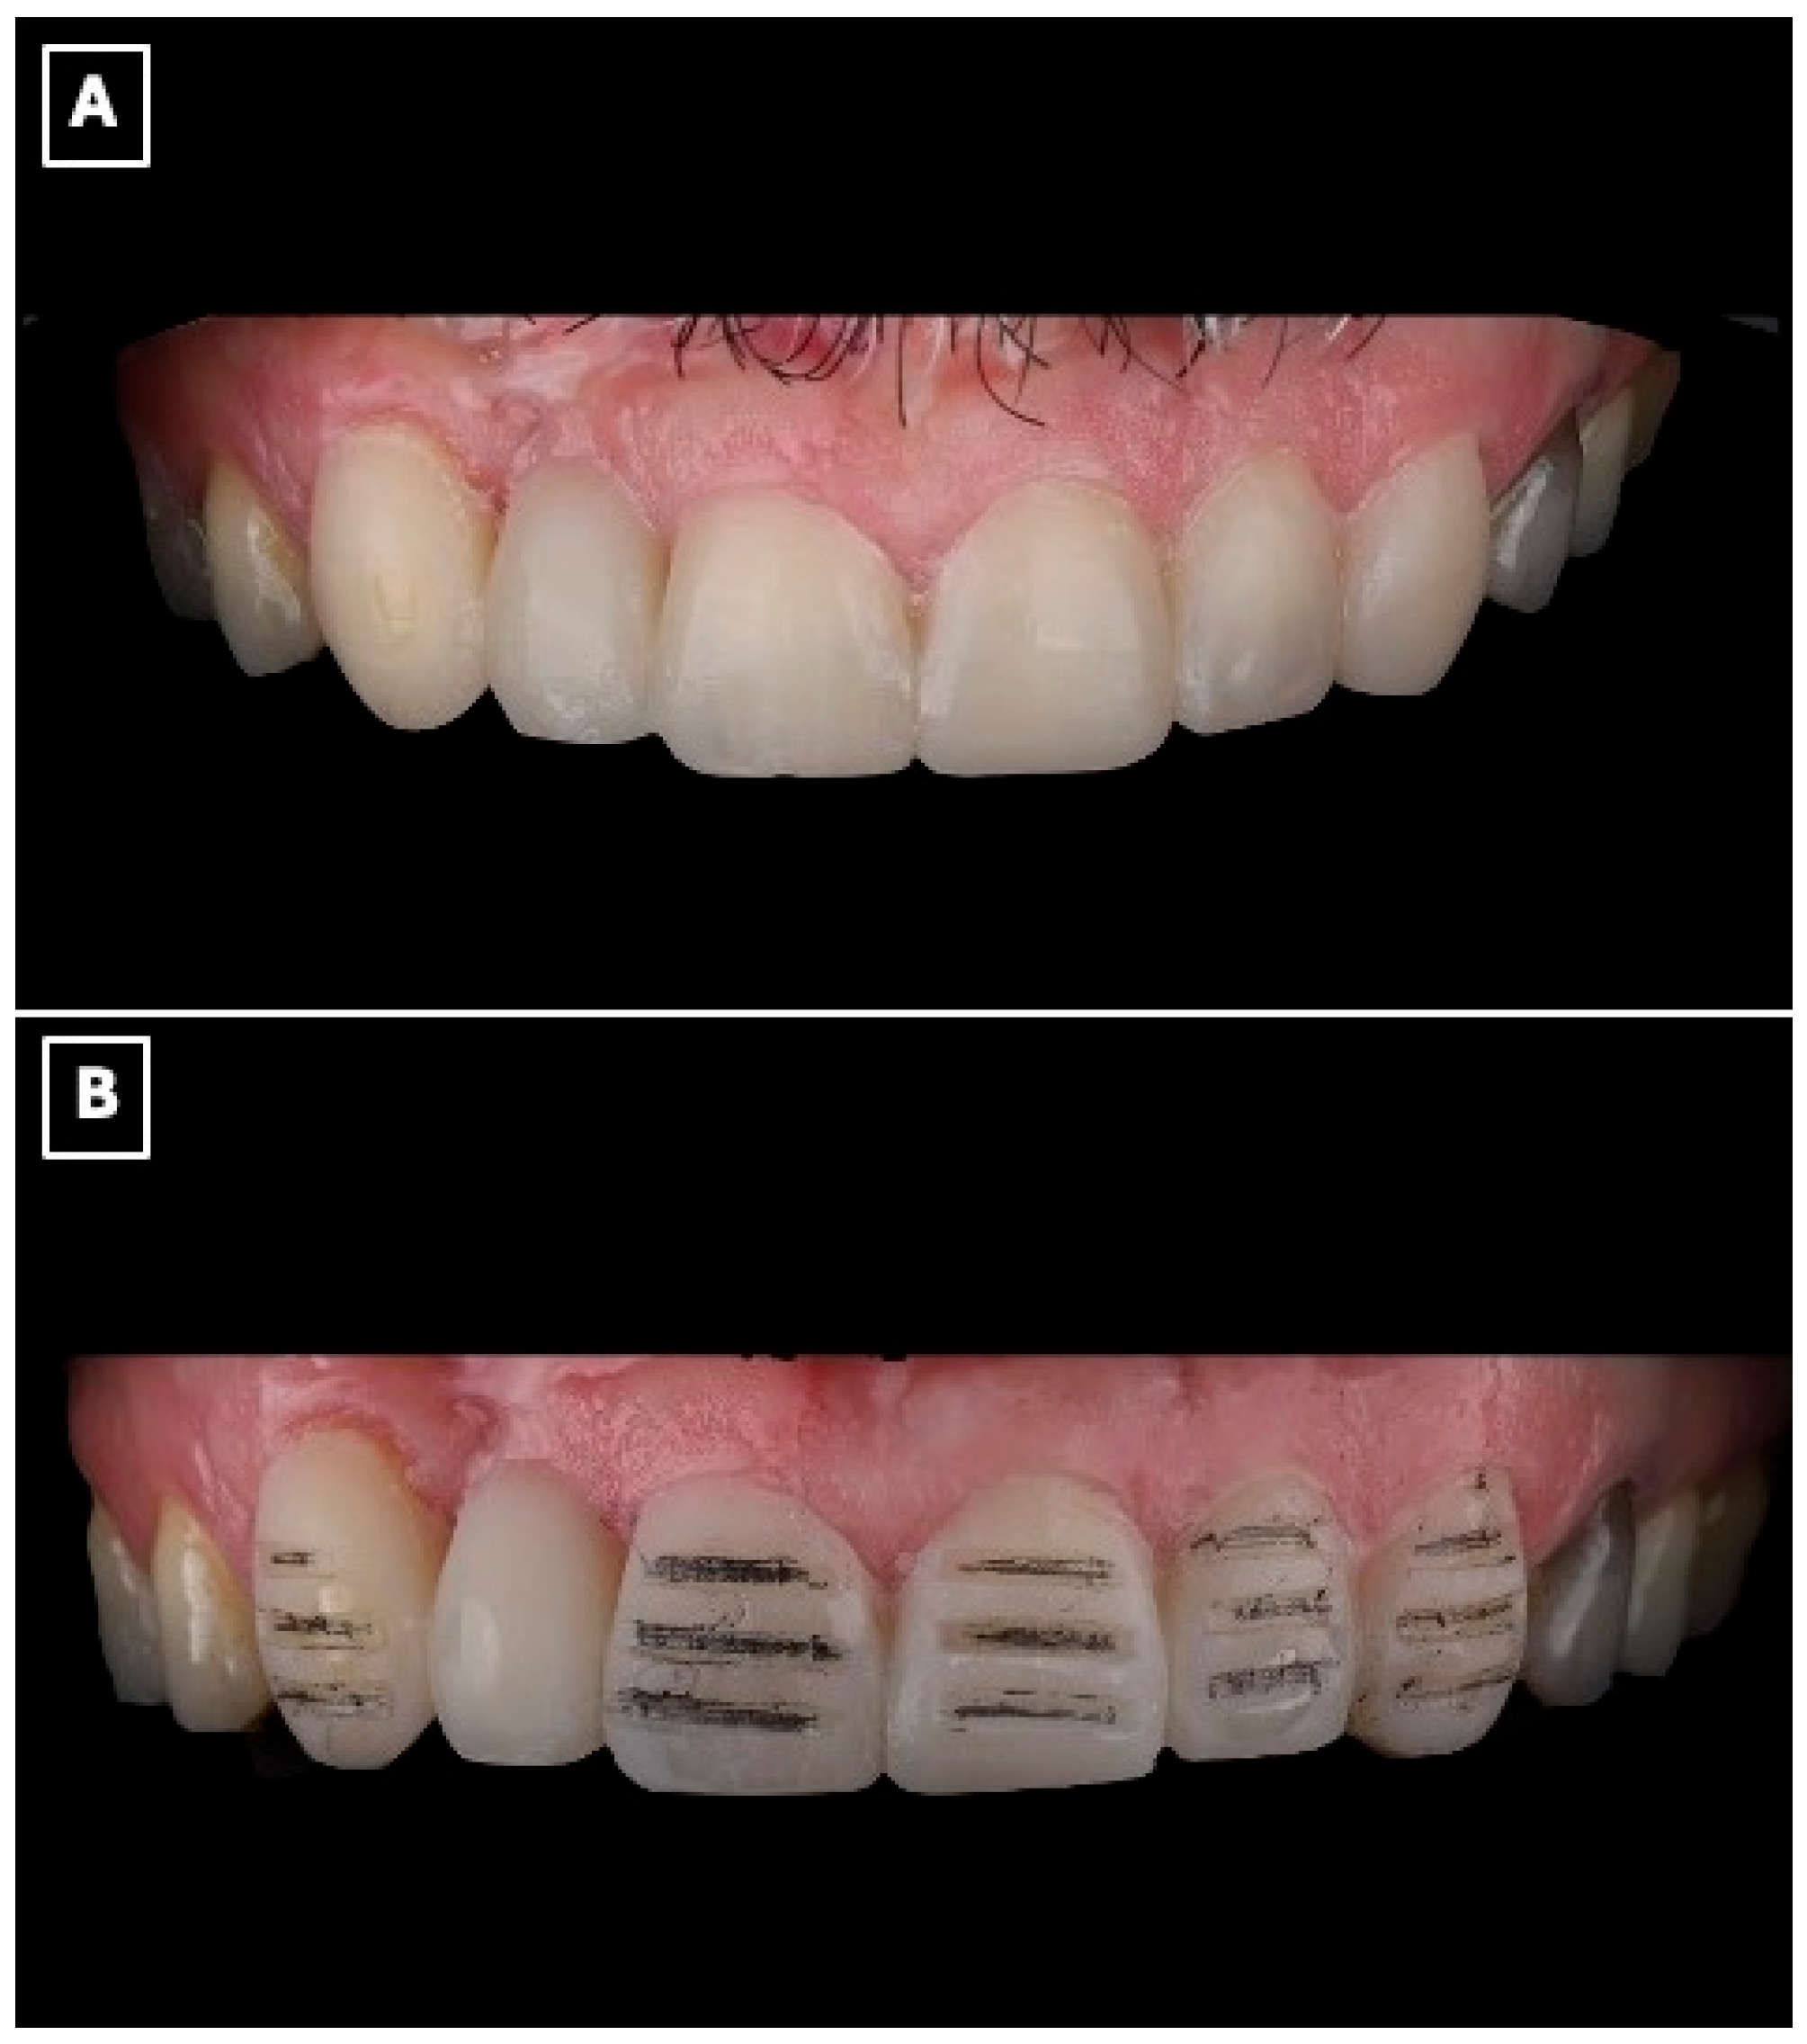

Figure 3.

Digital wax-up used for esthetic analysis and prosthetic planning of the anterior rehabilitation. (A) Virtual representation of the maxillary anterior region before wax-up, serving as a baseline for evaluating tooth position, incisal edge discrepancies, and space availability for the planned resin-bonded fixed dental prosthesis. (B) Digital wax-up design illustrating the proposed single-retainer cantilever resin-bonded fixed dental prosthesis and laminate veneers, with idealized tooth proportions, incisal edge position, and symmetry used to guide enamel-confined tooth preparation, pontic emergence profile, and overall esthetic integration within the smile.

Tooth preparation was performed under mock-up guidance to ensure minimal enamel reduction and to create optimal enamel-bonding surfaces (Figure 3B). Final impressions were obtained using a polyvinyl siloxane impression material (Imprint™ 4 PVS, 3M ESPE, St. Paul, MN, USA) and submitted to the dental laboratory for definitive fabrication.

Beyond its role in visualization, the digital wax-up and intraoral mock-up contributed directly to clinical decision-making and execution. The digitally planned wax-up enabled precise control of tooth proportions, incisal edge position, and pontic emergence profile, facilitating enamel-confined preparation and preservation of sound tooth structure. The intraoral mock-up functioned as a reduction guide during tooth preparation, minimizing unnecessary enamel removal and reducing chairside adjustments at the time of prosthesis seating. This digital-to-clinical transfer enhanced treatment predictability by allowing preoperative verification of esthetics and function, thereby improving clinical efficiency and patient acceptance.

The definitive restoration was fabricated as a full-contour lithium disilicate prosthesis using a low-translucency ingot (IPS e.max Press, Ivoclar Vivadent, Schaan, Liechtenstein). The prosthesis incorporated a single-retainer cantilever design with a modified ridge-lap pontic to optimize esthetics, biomechanics, and hygiene (Figure 4A,B). The single-retainer configuration was deliberately selected to eliminate differential abutment mobility and reduce interfacial shear stresses commonly associated with fixed-fixed designs. The palatal retainer was confined entirely to enamel and designed with smooth, well-defined margins to maximize adhesive bonding while preserving sound tooth structure (Figure 4B). Connector dimensions were carefully controlled to provide adequate fracture resistance without over-contouring, balancing mechanical strength with esthetic requirements. A modified ridge-lap pontic design was employed to achieve a natural emergence profile while maintaining a cleansable contour, allowing passive tissue contact and facilitating effective oral hygiene (Figure 4A,B).

Figure 4.

Definitive lithium disilicate single-retainer cantilever resin-bonded fixed dental prosthesis illustrating key design features. (A) Labial view showing the esthetic integration of the restoration within the anterior smile zone and the single-retainer cantilever configuration, selected to eliminate differential abutment mobility and reduce interfacial shear stresses at the adhesive interface. (B) Palatal view illustrating the enamel-bonded palatal retainer with a defined connector region and a modified ridge-lap pontic design, providing controlled tissue contact for esthetics while facilitating oral hygiene access and minimizing plaque accumulation at the pontic-tissue interface.